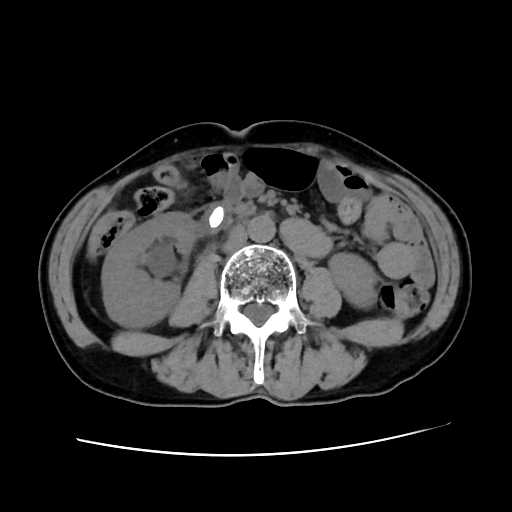

CT検査

内科領域

腹部

尿管結石